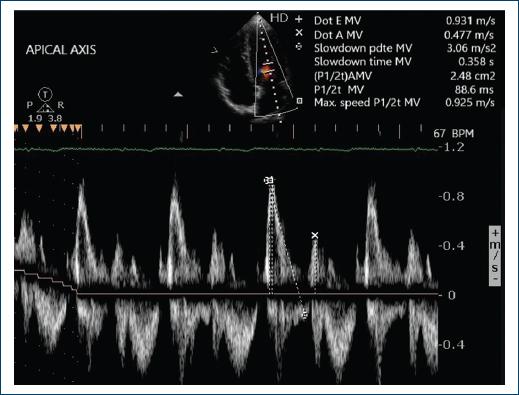

Figure 2 The transmitral flow is seen, which is constant and has a normal I/A ratio, indicating that the diastolic function is normal.

At present, the patient is hemodynamically stable, in an outpatient cardiology consultation, follow-up is carried out with laboratory studies, electrocardiogram, M-mode, two-dimensional and Doppler echocardiography, 24-h Holter study, and BP auto-monitoring (BPAM). The results of the M mode, two-dimensional, and Doppler mode echocardiogram in the mitral valves demonstrated an E-F slope of 163 mm/s, D-E distance of 19 mm, E-septum distance of 5 mm, and thickness of the anterior valve of 4 mm, in the Doppler mode a slight insufficiency is observed, with thickened, elongated, and redundant valves that condition a slight prolapse of the anterior valve, diastolic thickness of the posterior wall of 7 mm, and ejection fraction were calculated by Teicholz method with 78% of ejection fraction. Circumferential shortening fraction of 42%, tri cuspid ring velocity of 14 cm/sec, basal of 25 mm, medium segment of 24 mm, and length of 57 mm. Normal global and segmental mobility at rest was found. The systolic pressure of the pulmonary artery was 28 mmHg. There were no atrial dilation, or evidence of masses, thrombi or shunt.